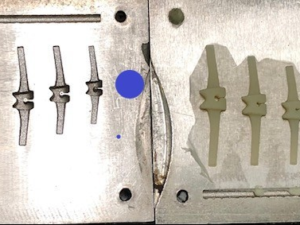

Vật liệu: vật liệu y sinh PEEK

Công nghệ: công nghệ in 3D

Vật liệu: vật liệu y sinh PEEK

Công nghệ: công nghệ in 3D